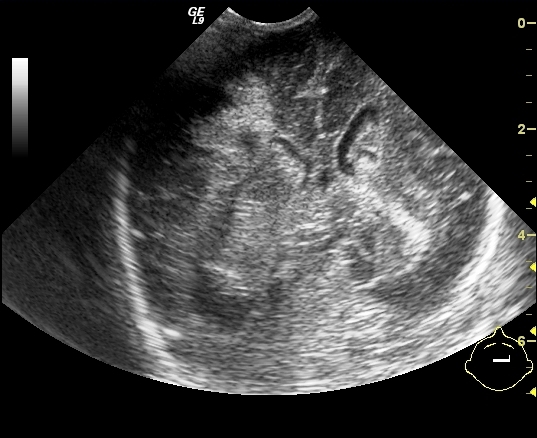

Malrotation-volvulus. During the normal development of the intestinal tract, the intestinal loops make three 90 degree clock-wise rotations around the mesenteric superior artery (MSA.) If this rotation only partially occurs during the embryonic development the intestines remain in a non-rotational or malrotational position, the mesenteric root will be shorter and the cecum will be weakly attached. This anatomic positioning can be symptom free throughout a lifetime, but it predisposes for volvulus. Volvulus can occur at any age, but it is most frequent in the first months of life, when it abruptly occurs with acute bilious vomiting. In this state the intestines around the mesenteric root twist, end up in a complete obstruction that can lead to a rapid death of the intestines. Ultrasonography can depict the mesenteric superior vein (MSV) coiled up around the MSA, so called “whirlpool”-sign.

14. “Whirlpool” sign The mesentery and the superior mesenteric vein, as it coils around the superior mesenteric artery. Volvulus. US exam.